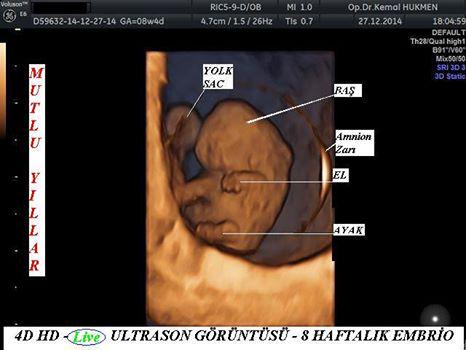

Kemal hükmen kadın hastalıkları doğum uzmanı hd live 3d 4d ultrason gebeli̇k taki̇bi̇ bebek sahi̇bi̇ olamama kizlik zari tami̇ri̇.